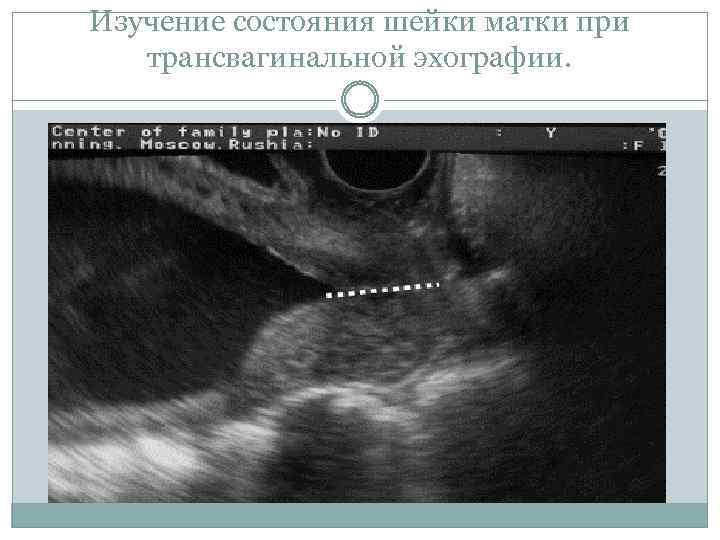

С помощью УЗИ получают ценную информацию о состоянии шейки матки во время беременности и о риске преждевременных родов. При трансвагинальной эхографии, которая имеет существенные преимущества перед пальцевым исследованием шейки матки и трансабдоминальной эхографией, возможно определение длины шейки матки на всём протяжении, состояния внутреннего зева, цервикального канала (рис. 11 -3).

Изучение состояния шейки матки при трансвагинальной эхографии.